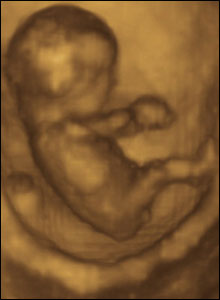

22 weeks gestation, 21 cm from crown to rump.

3 of 10

At 22 weeks gestation babies are capable of fine hand and finger movements. In a short space of time this baby scratches, rubs and pats his cheek before doing the same to his nose.